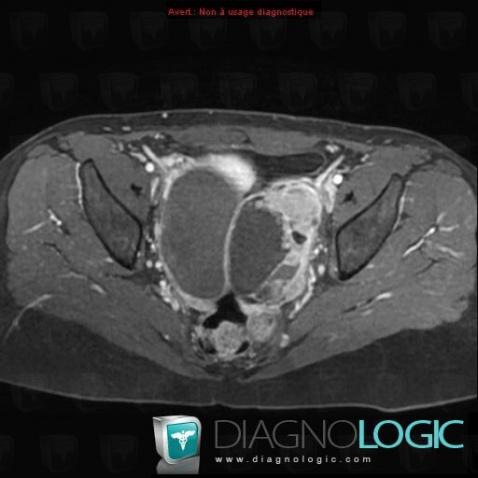

Serous cysteadenocarcinoma, Adnexa / Ovary fallopian tube, MRI

Here is the specific information in the key image above:

- Diagnosis Serous cysteadenocarcinoma, Location(s) Adnexa / Ovary fallopian tube, with gamuts T1 WI hyperintense adnexal mass